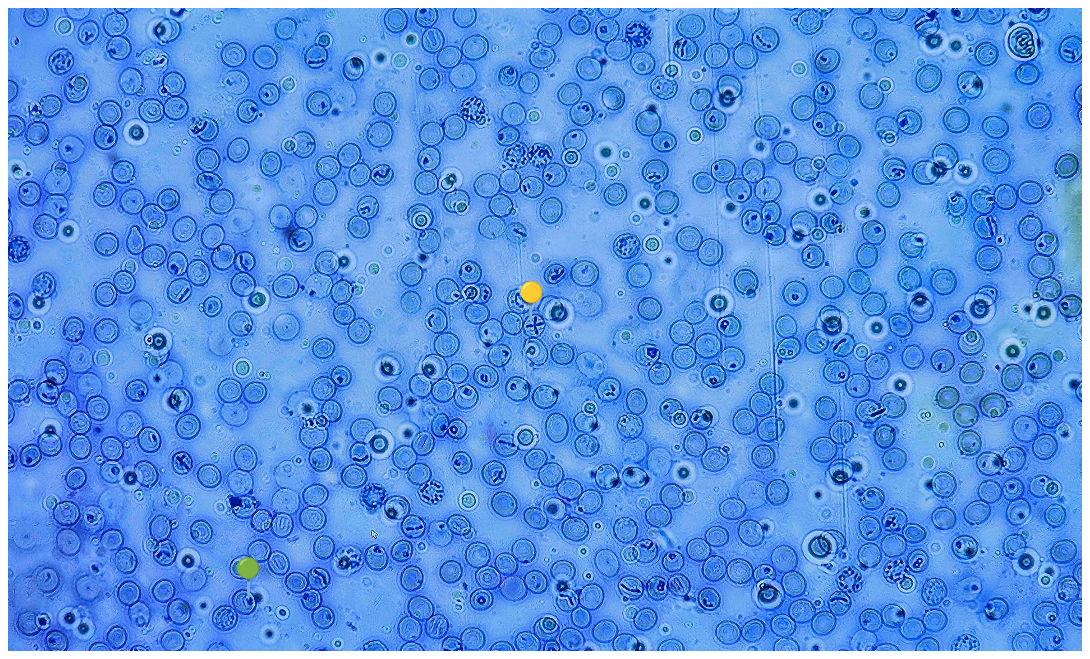

💠💍 Babesia canis

🟡 - Tetrada merozoitów (krzyż maltański)

🟢- Stadium pierścienia

😷❓ Parazytoza: Babeszjoza